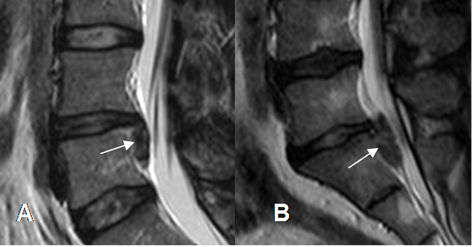

Fig 110. Regresión de hernia.

A y B: RM sagital en T2. Hernia mediana en L3-L4, que después de 7 meses, muestra disminución de su tamaño y menor compresión del saco dural. Cambios degenerativos en las placas terminales de L3-L4 y

L4-L5 y artefactos sobre el cuerpo de L4, ocasionados por materia de fijación posterior. (Puntas de flecha).